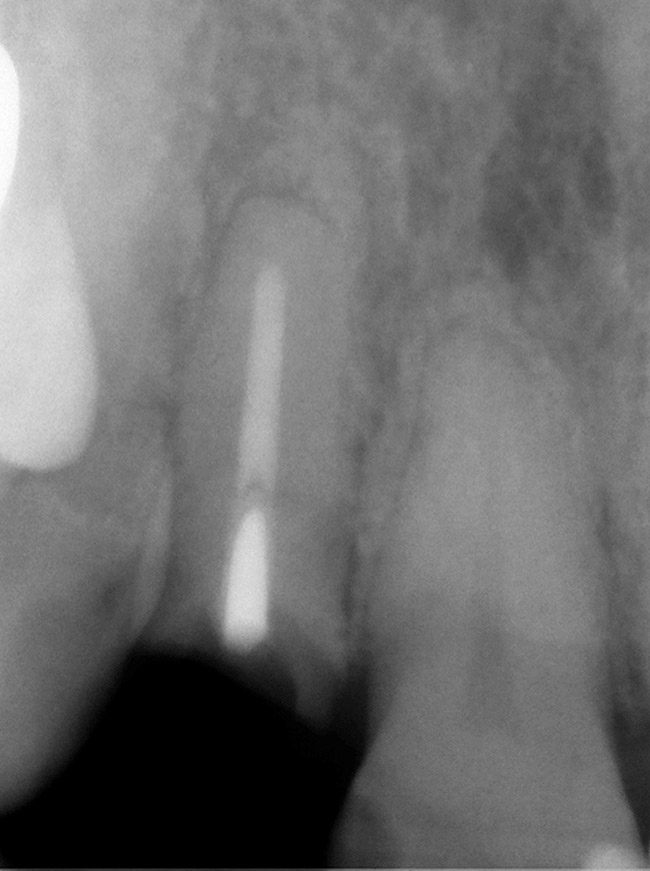

A 59-year-old woman presented with a recent history of trauma to her pre-maxilla, resulting in vertical root fracture of the maxillary left central incisor (Figure 1 and Figure 2). Examination revealed a mobile crown, moderate flat periodontal biotype, gingival margin of the left central incisor 1 mm coronal to that of the adjacent central incisor, central incisor tooth width discrepancy, and a medium smile line. The treatment plan included flapless extraction of the fractured tooth with the potential for simultaneous socket grafting using mineralized bone allograft (MinerOss®, BioHorizons, Inc, Birmingham, AL) and a free gingival graft (Figure 3) harvested from the left palate. Post-extraction examination revealed vertical labial plate loss of 2 mm and class I interproximal height of bone; therefore, all three procedures were performed. Four months postsurgery (Figure 4), a mid-crestal and sulcular incision without release was made to allow for crestal plasty and core biopsy (Figure 5). Histomorphometry revealed 87% vital bone with minimal evidence of residual allograft (Figure 6). This finding was consistent with type II bone density and allowed for non-submerged implant placement. The labial plate was completely regenerated. A provisional crown was placed and contoured to groom the soft tissue for 3 months (Figure 7), followed by final crown fabrication (Figure 8).

Figure 2  Periapical radiograph of the maxillary left central incisor with vertical root fracture.

Figure 2